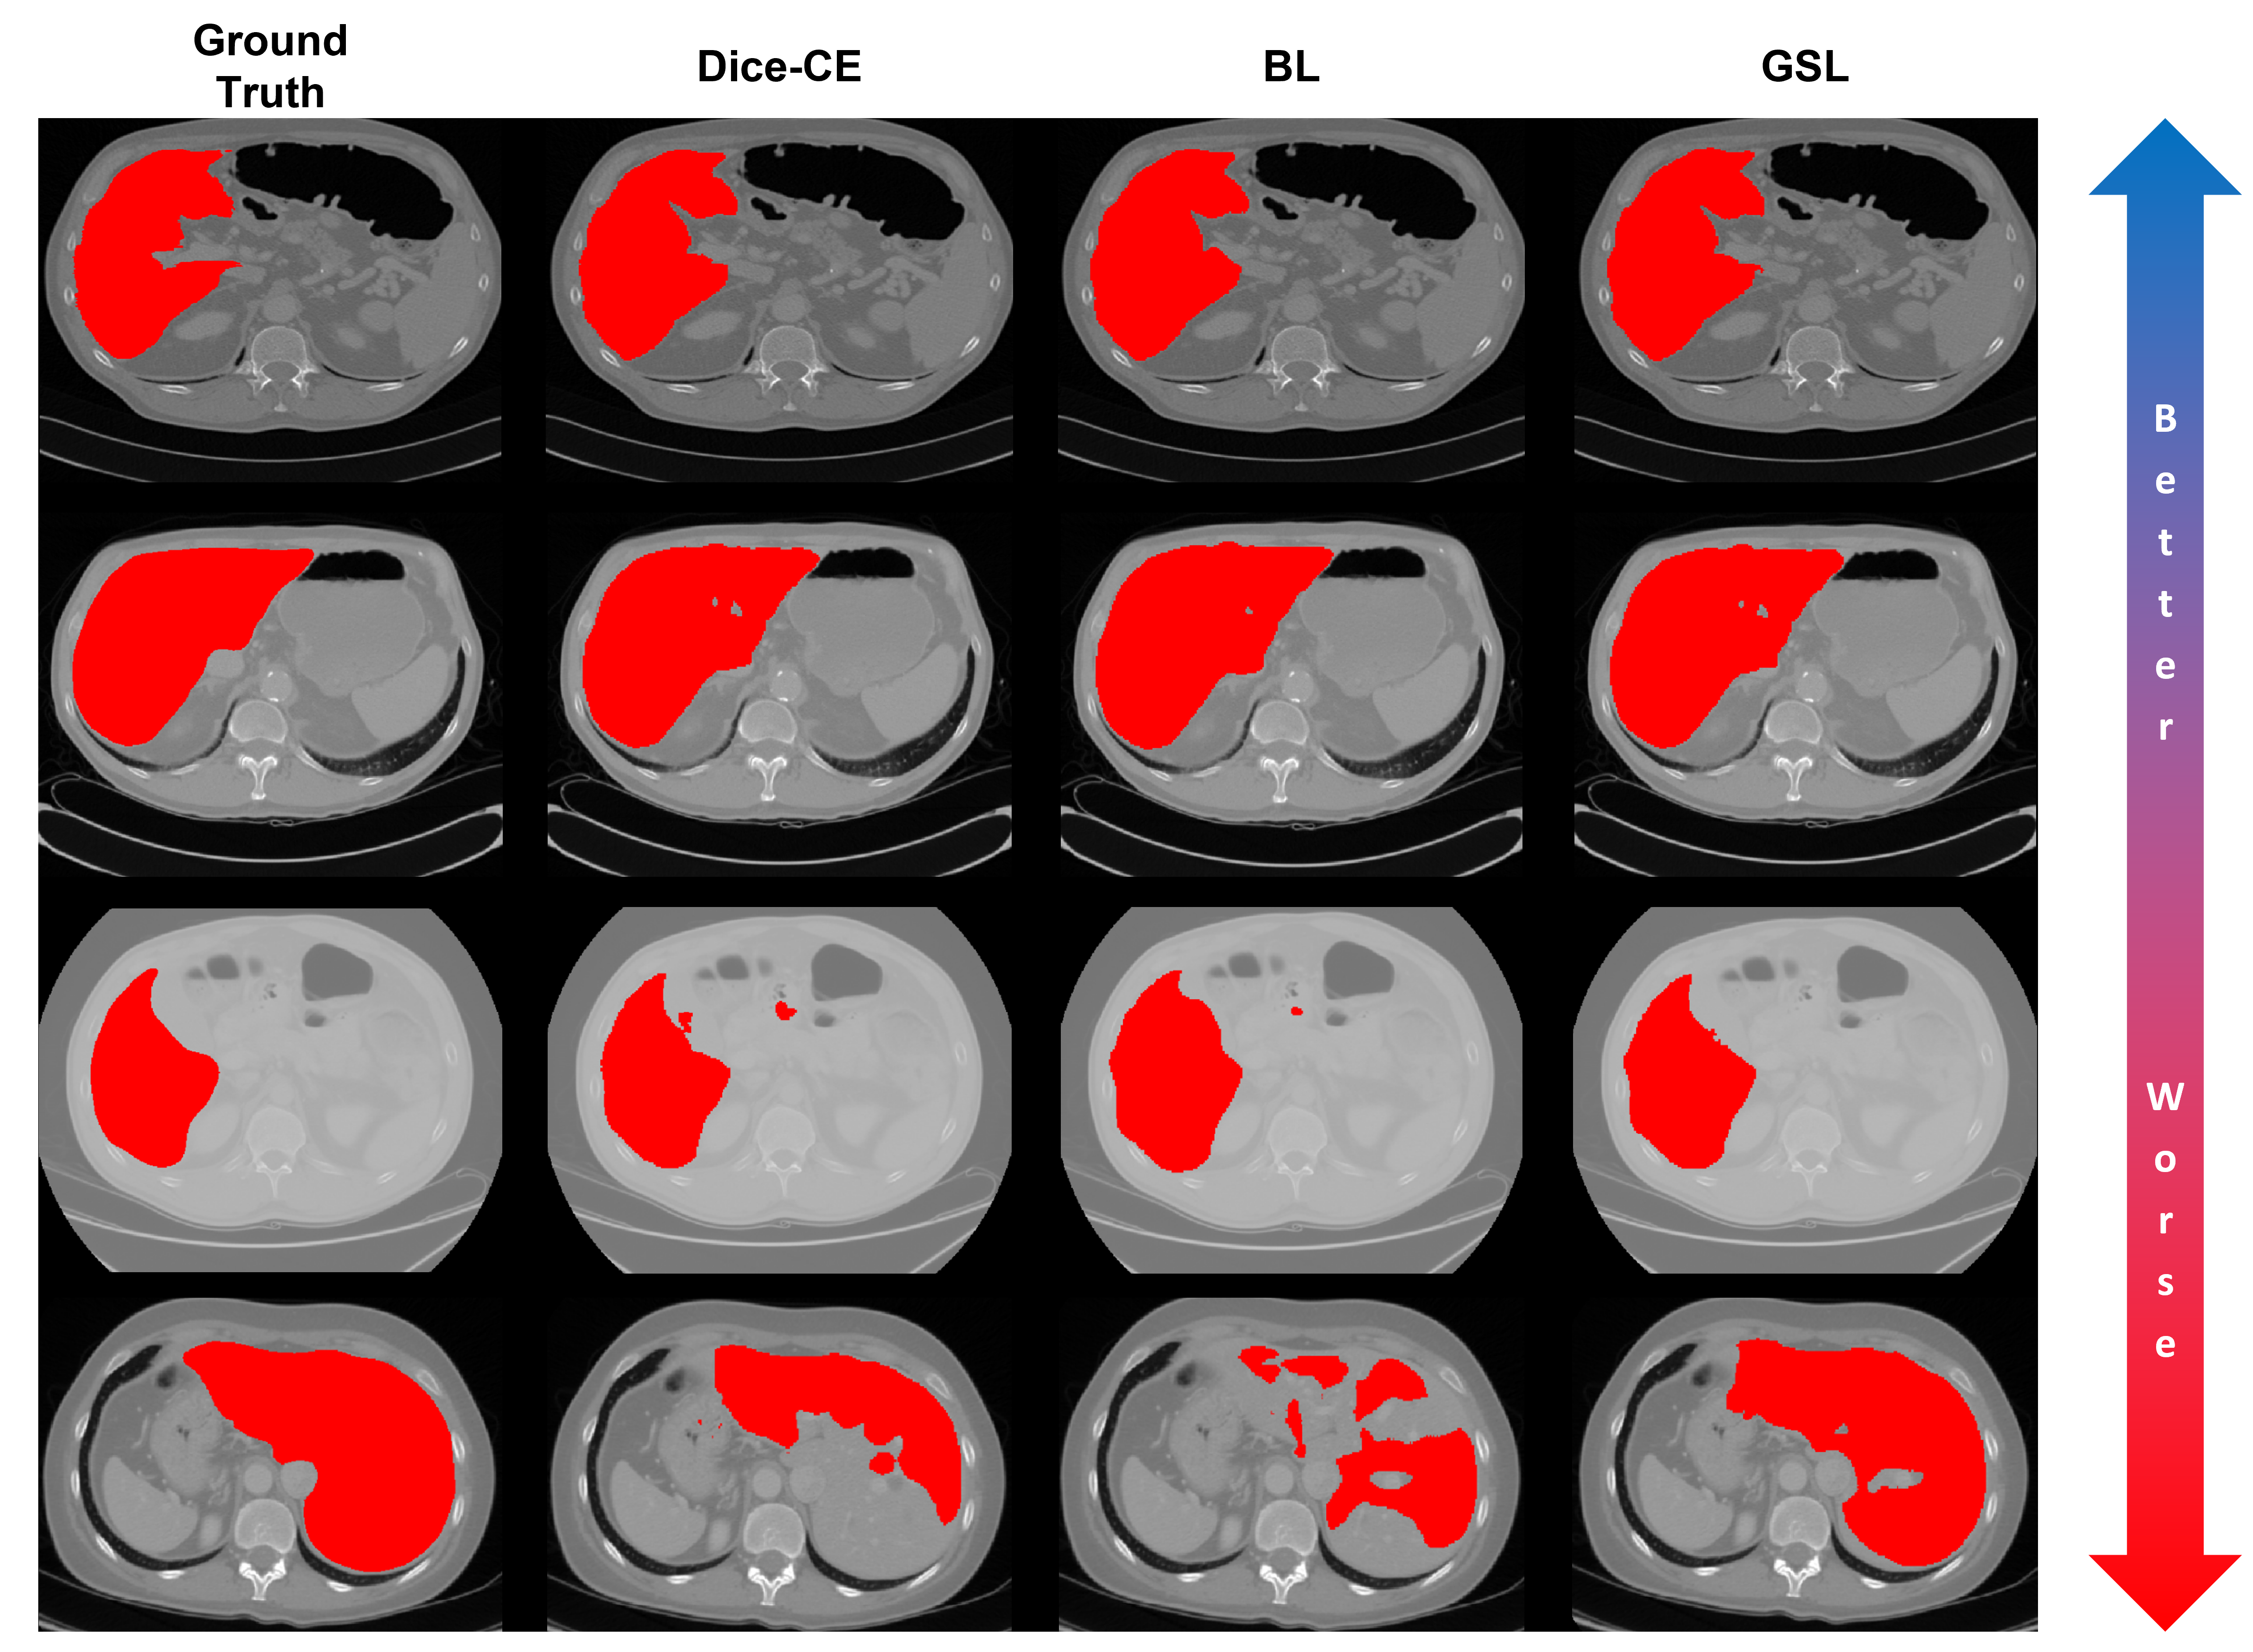

Using the methods described in Section 2, we train a nnUNet using each loss function described in Section 1.1 and compare their performance to our proposed GSL function. This experiment uses a linear schedule for the parameter α𝛼\alphaitalic_α in the boundary-based losses (i.e., HL, BL, and GSL). Table 1 shows the results of this comparison. Here, our GSL achieves lower Hausdorff 95 and average surface distances for the LiTS and BraTS challenge datasets. Figures 3 and 4 show from left to right the ground truth and predictions from the nnUNet architecture trained on LiTS and BraTS data respectively, with the Dice-CE, BL, and GSL functions for a spectrum of easier to more difficult test cases. Even for more difficult cases, we see that the GSL produces visually superior predictions than the Dice-CE and BL functions.

Figure 3: From left to right, ground truth and predictions from the nnUNet architecture trained on LiTS data with Dice-CE, BL, and GSL functions for a spectrum of easier to more difficult test cases. Here, we see that, even for more difficult cases, the GSL produces visually superior predictions than the Dice-CE and BL functions.